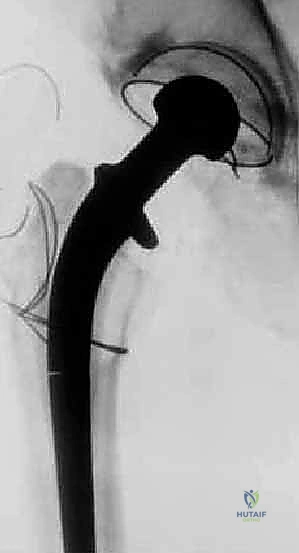

- الأشعة السينية التقليدية (X-rays): صور متعددة الزوايا لتقييم التآكل العظمي، هجرة المكونات، وتحديد تصنيف فقدان العظم (مثل تصنيف Paprosky).

- الأشعة المقطعية (CT Scan): ضرورية للغاية لتقييم مخزون العظم الحُقّي (في الحوض) وتحديد حجم التجاويف العظمية بدقة ثلاثية الأبعاد. تساعد في التخطيط لاستخدام دعامات معدنية أو ترقيع عظمي.